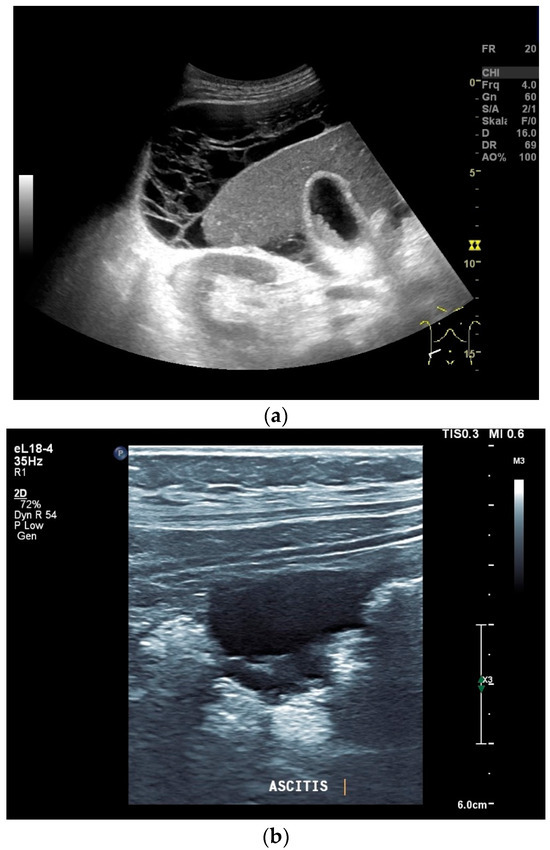

What can be seen sonographically? Ascites can be either diffuse or focal type [Figure 1a,b]. Due to the protein and cell content, these tend to be echogenic, rather than non-echoic. Attention must be paid to enlarged lymph nodes at the same time. Any thickening of the peritoneum and mesentery must be specifically searched for. This also applies to macronodular changes in the peritoneum and mesentery [Figure 1c–h]. The smallest speck-like deposits are usually not visible on ultrasound [36]. With ascites, it may be possible to observe the adhesions [31,37]. Kumar et al. were able to histologically detect granulomatous inflammation in 17/19 (89%) patients using ultrasound-guided needle biopsy of omental thickenings. In a country like India, the authors interpreted this as a manifestation of tuberculosis [32].

Figure 1.

Typical changes in the peritoneum, mesentery, and omentum in patients with tuberculosis. Ascites with pronounced septa (a). Ascites encapsulated between the abdominal wall and colon (b). Omental thickening with non-echoic caseous abscesses and few echogenic contents (c); hypoechoic nodules in hyperechoic thickened peritoneum (d). Significantly thickened hyperechoic peritoneum in B-mode US (right side of image) (marked with arrows). In CEUS, the thickened peritoneum is contrast enhanced in the arterial phase (e). In the parenchymal phase, it shows a decrease in enhancement (f). The thickened hyperechoic peritoneum shows a non-echoic lesion (arrow) (g). In the CEUS, this is not enhanced and instead shows a hyperenhanced rim. This corresponds to caseous necrosis (h).